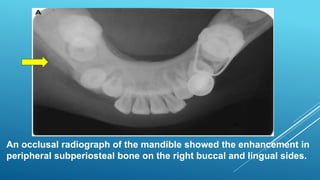

An occlusal radiograph of the mandible showed the enhancement in

peripheral subperiosteal bone on the right buccal and lingual sides.

Chronic Osteomyelitis with Proliferative Periostitis

 Radigraphs show focal subperiosteal

overgrowth of bone with smooth surface on

outer cortical plate.

 The subperiosteal mass consists of irregular

trabeculae of actively forming woven bone with

scattered chronic inflammatory cells in fibrous

marrow.